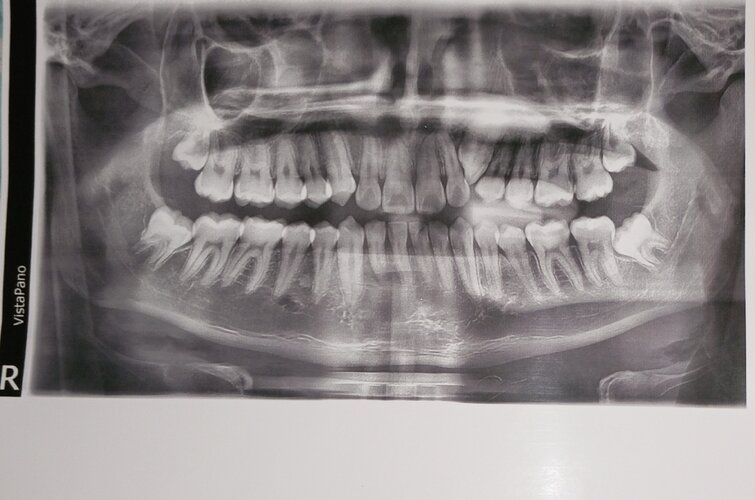

Hello, my orthodontist told me that I had to extract premolars because I don't have enough space and I have a trapped canine that hasn't come out. Should I remove the premolars? This is a doubt that has been on my mind.

(I will post my panoramic x-ray so you can help me)

(I will post my panoramic x-ray so you can help me)